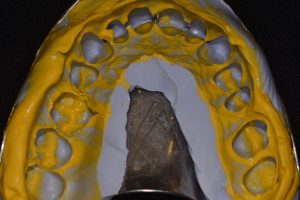

- Ryc. 1_Łącznik gojący dwuczęściowy do systemu Ankylos, strona okluzyjna.

- Ryc. 2_Łącznik gojący dwuczęściowy do systemu Ankylos, strona policzkowa.

- Ryc. 6_Wycisk na łyżce zamkniętej masą polieterową przed repozycjonowaniem transferu wyciskowego.

- Ryc. 7_Transfer wyciskowy wraz z repliką implantu zamontowany w wycisku zamkniętym.

- Ryc. 8_Wycisk zębów przeciwstawnych masą silikonową.

Osiągnięcie dobrego efektu funkcjonalno- -estetycznego wymaga zastosowania odpowiedniej śruby gojącej. Dobrym rozwiązaniem jest zastosowanie szerokiego łącznika gojącego modelującego tkanki miękkie, aby stworzyć jak najbardziej anatomiczny kształt przyszłej korony. Ponieważ dokładność każdej z metod wyciskowych nie jest idealna, w pierwszym etapie zawsze pobieramy łatwiejszy do wykonania wycisk z poziomu implantu metodą łyżki zamkniętej, rejestrat zwarciowy oraz wycisk zębów w łuku przeciwstawnym. Istotnym elementem jest przekazanie do laboratorium informacji dotyczących tkanek miękkich (biotyp) oraz określenie, jak głęboko poniżej poziomu kości wyrostka zębodołowego znajduje się płaszczyzna protetyczna implantu. Praca na tym etapie trafia do laboratorium protetycznego, gdzie modele są odlewane i montowane w artykulatorze. Model, który będzie skanowany zawiera analog implantu i maskę dziąsłową.